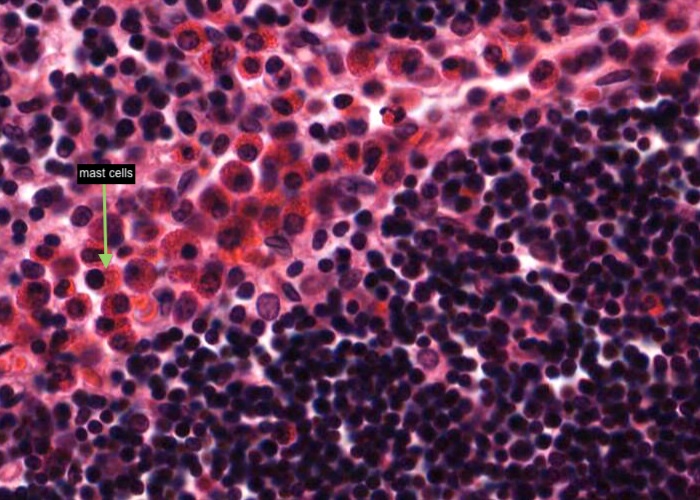

Mast cells with very prominent red-stained granules in their cyoplasm are common at the boundary of the thymus cortex and medulla.